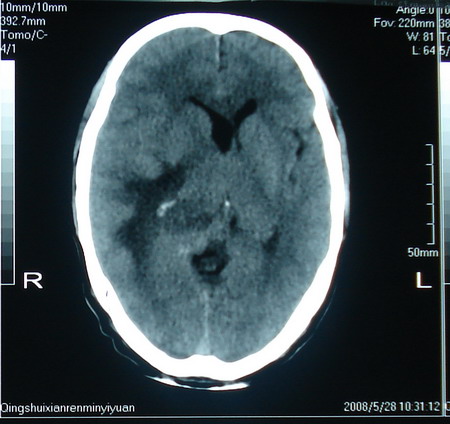

标题: CT13794:M63Y,头颅CT平扫 [打印本页]

标题: CT13794:M63Y,头颅CT平扫

男,63岁,头痛,呕吐,意识模糊一周。无发烧及感染史。

胶质瘤

胶质瘤可能性大。

支持恶性胶质瘤,增强

胶质母细胞瘤

小肿瘤大水肿,考虑转移瘤

支持右侧丘脑恶性胶质母细胞瘤可能性大,建议增强进一步检查。